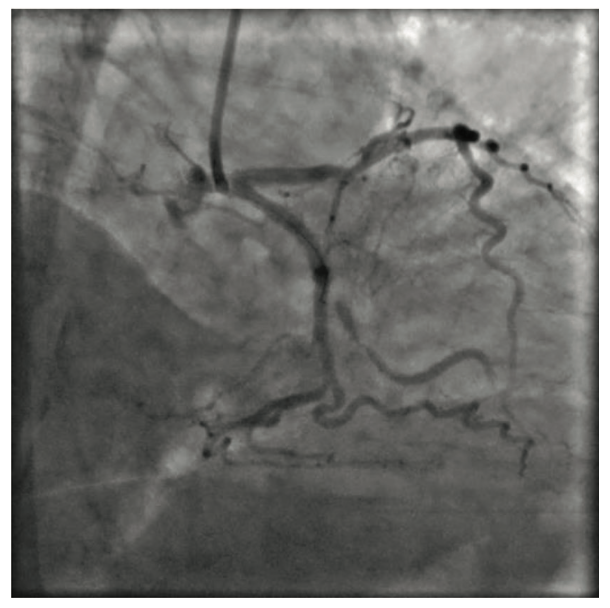

A Balance Middleweight (BMW) wire (Abbott Vascular), followed by a Hi-Torque Whisper guidewire (Abbott Vascular) failed to cross the lesion due to the severity of stenosis and the angulated take-off of the OM. The angulation was tackled with an additional curve on the Whisper wire’s tip, by itself and then in combination with a 90-degree angled SuperCross microcatheter (Teleflex). The Hi-Torque Whisper wire was able to enter the ostium of the OM by parking the microcatheter with its tip parallel to the ostium; however, it still failed to cross the lesion. The tip would enter the lesion and then buckle and bounce off into the main circumflex due to the severity of stenosis, which appeared to be 100% (Figure 1, Video 1). The presence of brisk antegrade flow in the OM distal to the stenosis was convincing for an invisible microchannel available across the occlusion; therefore, we decided to utilize the ability of the fluid contrast agent to find the microchannel. We positioned the wire at the occlusion and injected 10 cc of contrast with high manual pressure, effectively replacing the blood in the microchannel with the lower viscosity contrast agent, and captured the scene under cine angiography. At this time, the wire was inside the SuperCross microcatheter, which allowed the wire to float inside the microcathether without resistance by the Copilot Bleedback Control valve (Abbott Vascular), which was tight around the microcatheter. Simultaneous to contrast agent injection by the assistant, the operator advanced the wire very slowly and let the wire float itself, along with the contrast agent, across the uncrossable microchannel into the distal OM1 (Figure 2A-B, Video 2). The proposed mechanism is the replacement of red blood cells (RBC) by the contrast media mixing with blood. Once the wire crossed the lesion, the rest of the case was expeditiously completed with angioplasty and stenting of the OM.